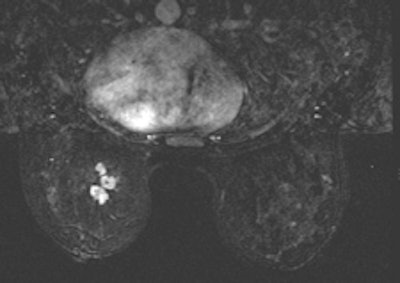

According to the 2013 American College of Radiology (ACR) guidelines, breast MRI should be performed for screening high-risk patients, as well as those with a new breast malignancy, following a 2007 report in the New England Journal of Medicine on MRI's ability to find cancer in the contralateral breast. It should also be used to screen patients with breast augmentation, which presents difficulties such as mammographically occult regions, or cancer tracking the contour of the implant, Shaheen said.

For confirmed cancers, MRI can be used to assess the extent of disease such as ductal carcinoma in situ, for additional evaluation of imaging or clinical findings, and for problem-solving.

MRI may change patient management, but it is not a primary screening modality, Shaheen said.

"Breast MRI is not a substitute whatsoever for other modalities or biopsy," she said.